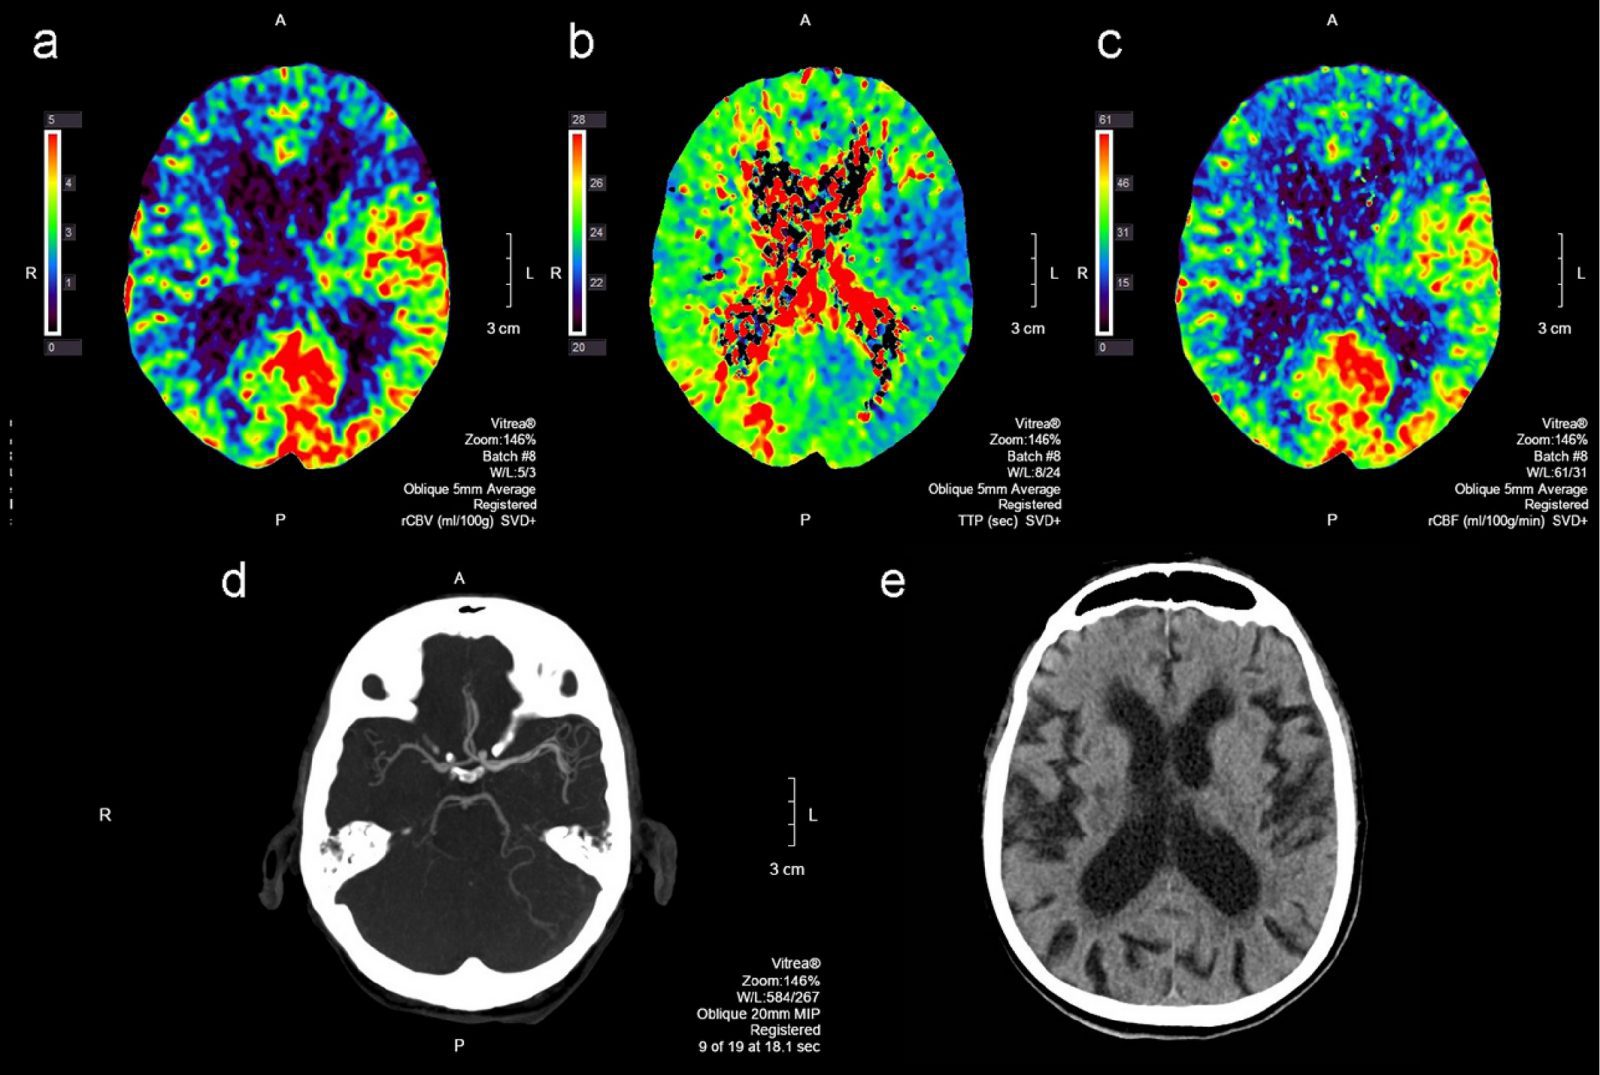

In the process of analysis of PCT maps, neuro-radiologists detect, measure, and describe the asymmetry between perfusion in left and right hemisphere of the patient. This process is currently done manually. In order to perform a perfusion image analysis, it is necessary to find the lines that separate the left brain hemisphere from the right one. Statistical evaluation with region of interest measurements is also possible with the digital phantom, and the accuracy of the perfusion analysis can be determined by calculating correlations with true values, as well as error sources. Variations in the absolute values may be partly caused by the difference in basic algorithms, such as SVD and maximum slope, as well as other minor implementations in perfusion analysis.

There are several types of de-convolution that can be used for perfusion analysis. Singular Value Decomposition (SVD) algorithms are often viewed as the most accurate method because they do not rely on assumptions about the shape of the residue function. Some of the problems associated with standard SVD algorithms for brain perfusion are: noise sensitivity, inaccurate MTT values due to autoregulation or collateral flow, and inability to account for natural blood flow dynamics.

Cerebral perfusion analysis is used in neuro-radiology to assess tissue level perfusion and delivery of blood to the brain and/or tissues of the head. A perfusion CT study involves sequential acquisition of CT sections during intravenous administration of an iodinated contrast agent. The procedure involves injecting a contrast agent into the individual. While investigators were instructed not to use the perfusion maps generated by the automated CT perfusion analysis software for decision-making regarding endovascular therapy, they could use their standard of care perfusion software for this purpose.